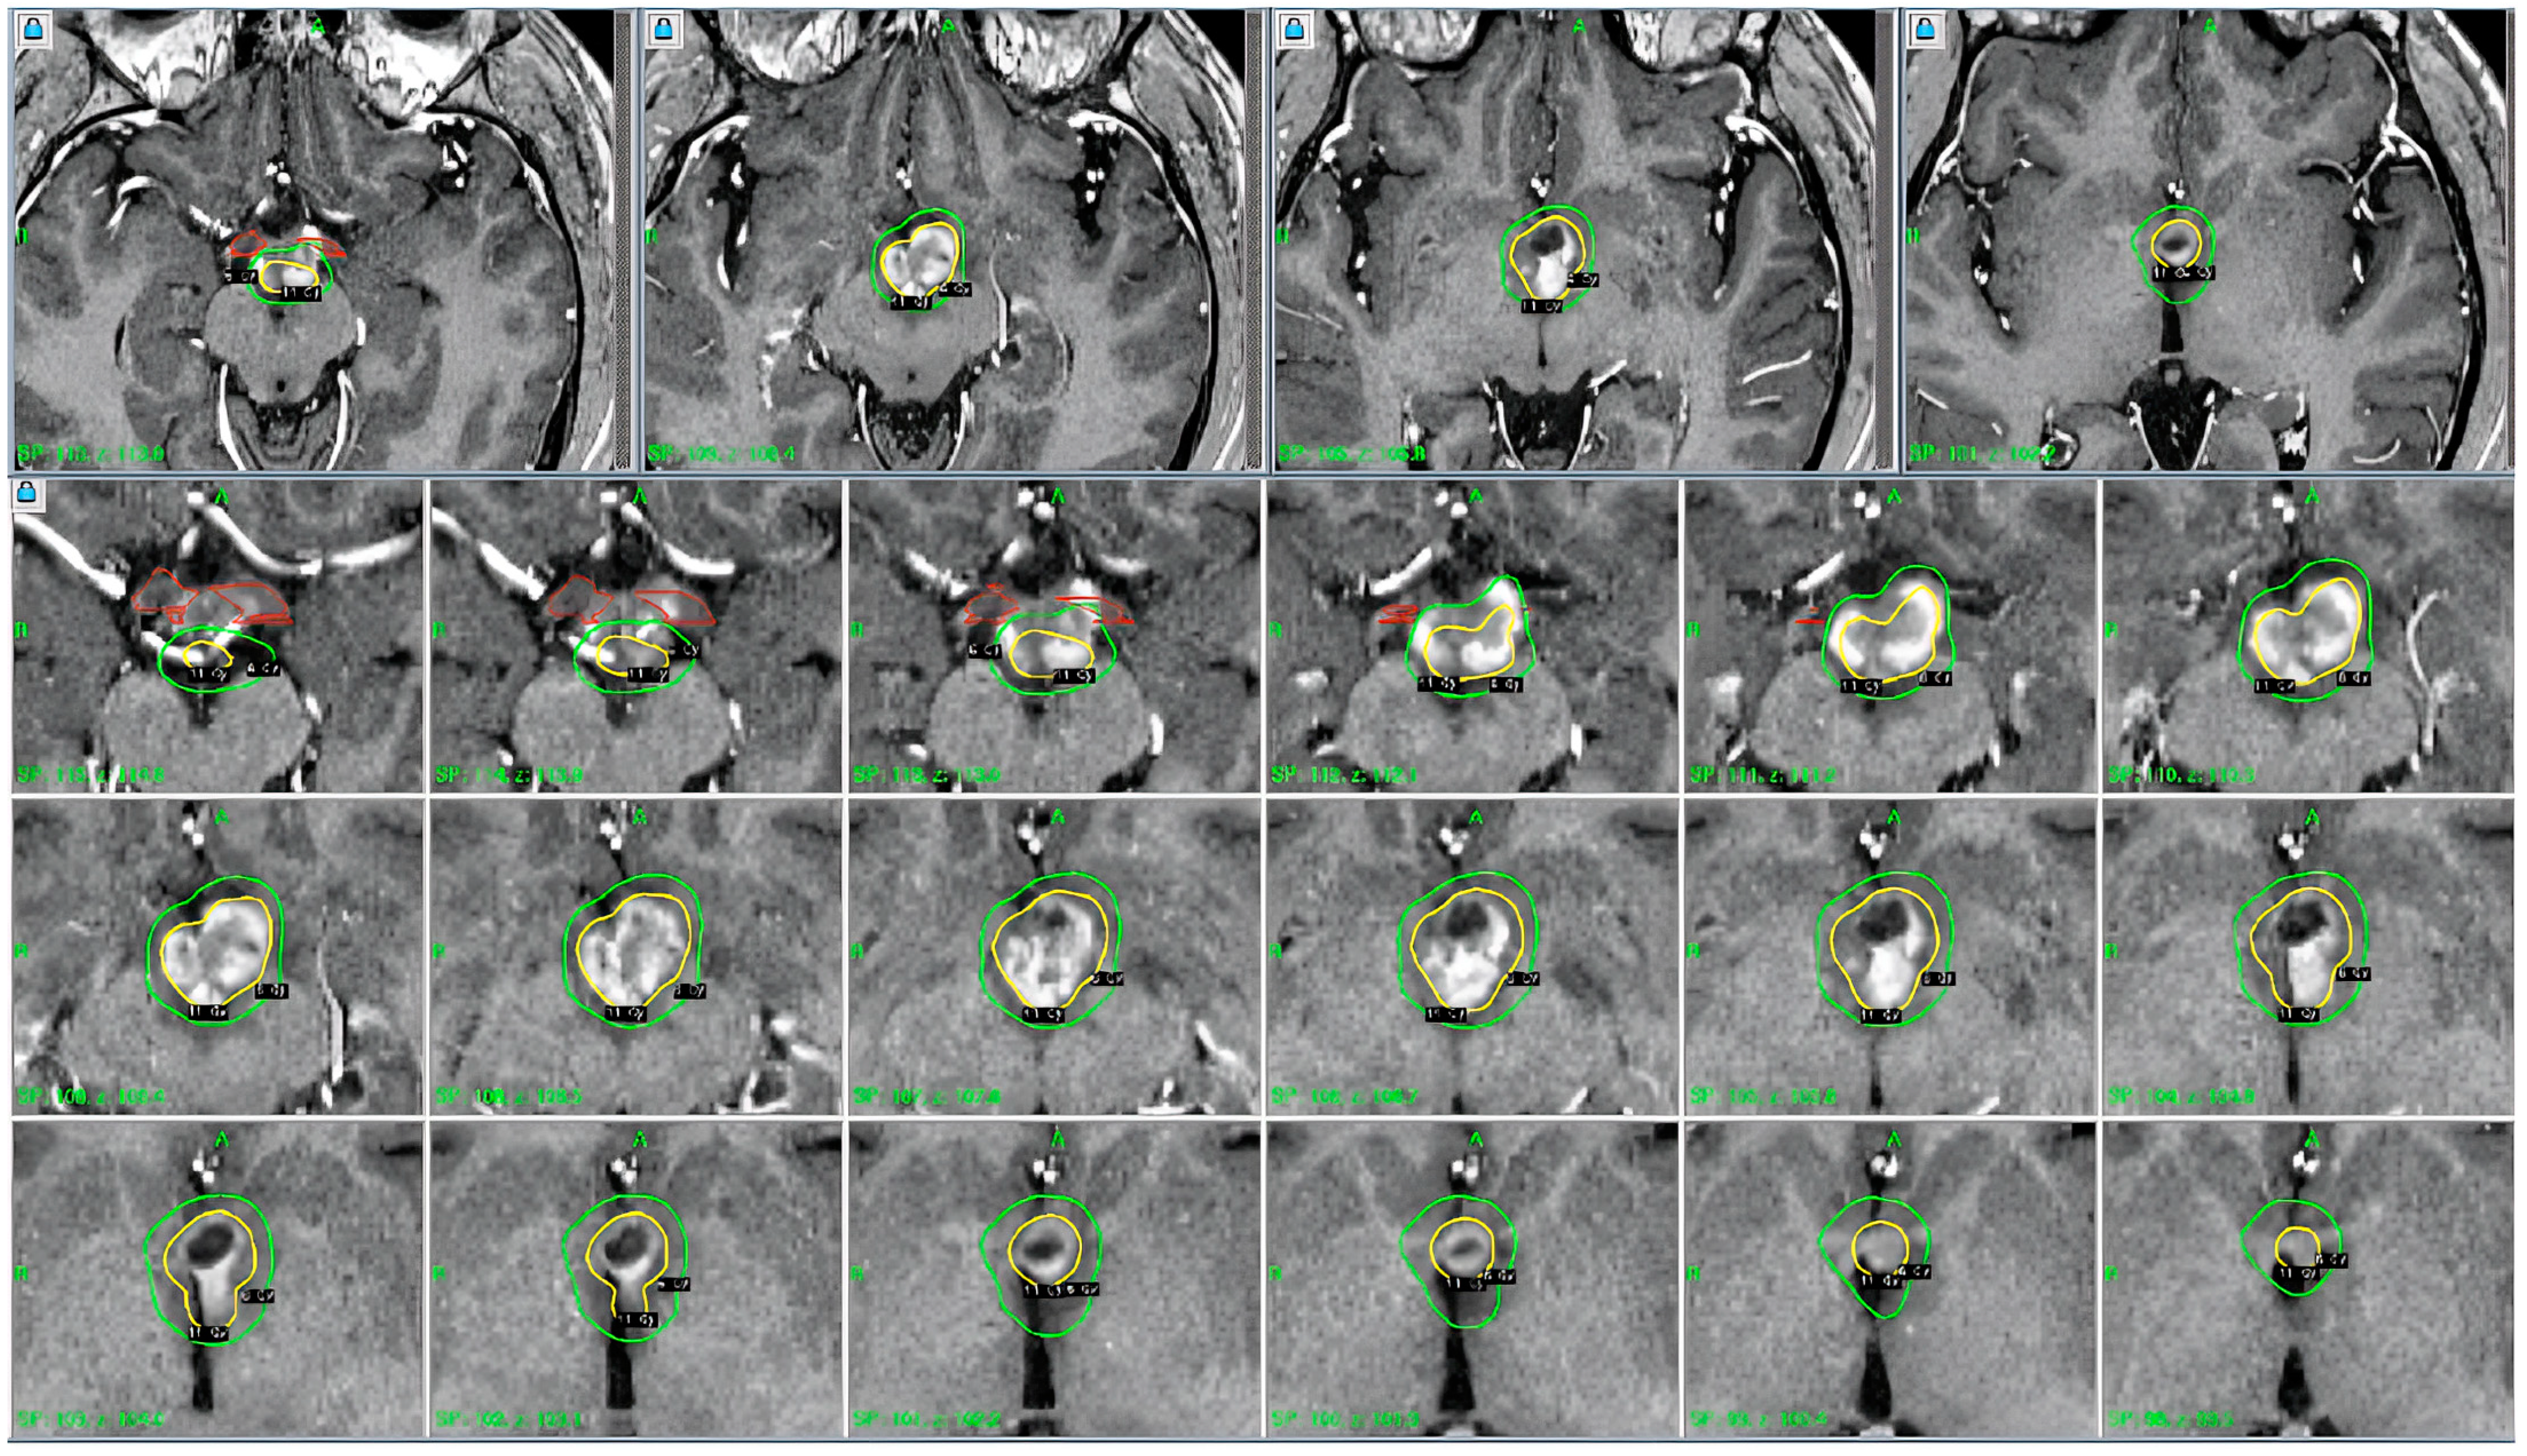

Figure 2. The patient underwent placement of the Leksell stereotactic head frame without difficulty. This was followed by obtaining a high-resolution stereotactic MRI scan of the brain. Contrast-enhanced T1-weighted axial images were obtained at 2 mm intervals. The images were transferred into the treatment planning workstation and reviewed. The previously identified enhanced lesions involving the hypothalamus were observed. Operative procedure: the team proceeded with outlining the visible lesion and developing a treatment plan. A single dose calculation matrix was used. The hypothalamic lesion was treated using 9 shots with 4 and 8 mm collimator helmets. The volume target was 2.6 cm3, and the prescription isodose was 11 Gy. White to the 50% isodose line. Note: 100% of the tumor received the prescription isodose. Brain stem < 11 Gy, left optic nerve < 7.8 Gy, and right optic nerve < 5.1 Gy.

GKRS was performed using advanced stereotactic navigation, which enabled precise delineation of the tumor margins while minimizing radiation exposure to the surrounding healthy tissues (Table 2). The radiosurgical plan was carefully developed to provide optimal dose coverage to the lesion while adhering to dose constraints for critical structures, particularly the optic chiasm, brainstem, and hypothalamus. A marginal dose of 14 Gy was delivered to the 50% isodose line, which provided an effective tumoricidal dose with minimal risk of radiation-induced complications. The precision afforded by stereotactic targeting was integral to achieving the therapeutic objectives, given the high sensitivity of the surrounding anatomy to radiation.

At the three-month follow-up following GKRS, the patient exhibited substantial clinical improvement (Figure 2). He no longer demonstrated symptoms of encephalopathy or lethargy, and his mental status had returned to “normal.” Furthermore, the patient’s neurological examination was unremarkable, and repeat MRI imaging demonstrated a significant decrease in tumor volume. Desmopressin therapy maintained satisfactory control of diabetes insipidus, and no new neurological deficits were identified (Figure 3). The efficacy of radiosurgery as a minimally invasive treatment option for hypothalamic gliomas is emphasized by these results, particularly in situations where conventional surgery demonstrates significant risks.